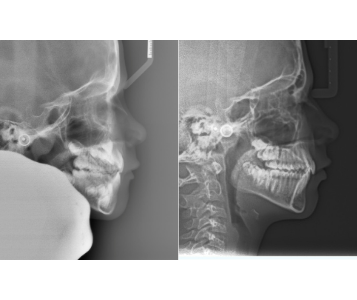

For children with smaller lower jaws, we use time-sensitive orthopedic appliances to guide the jaw forward into a more ideal position. This not only improves facial harmony but also lifts the hyoid bone, which supports the soft tissue airway — leading to better airflow and improved sleep quality.

3. 3D Growth Approach

Using 3D imaging and airway analysis, we can visualize the child’s airway, jaw structure, and growth direction. This allows for a comprehensive treatment plan that enhances both aesthetics and breathing function.

Before and After: Expanding the Airway, Expanding Possibilities

Our before-and-after cases clearly show the power of airway-driven orthodontics. After treatment, the palate is wider, the airway is larger, and the child experiences better sleep, improved focus, and enhanced overall wellness.